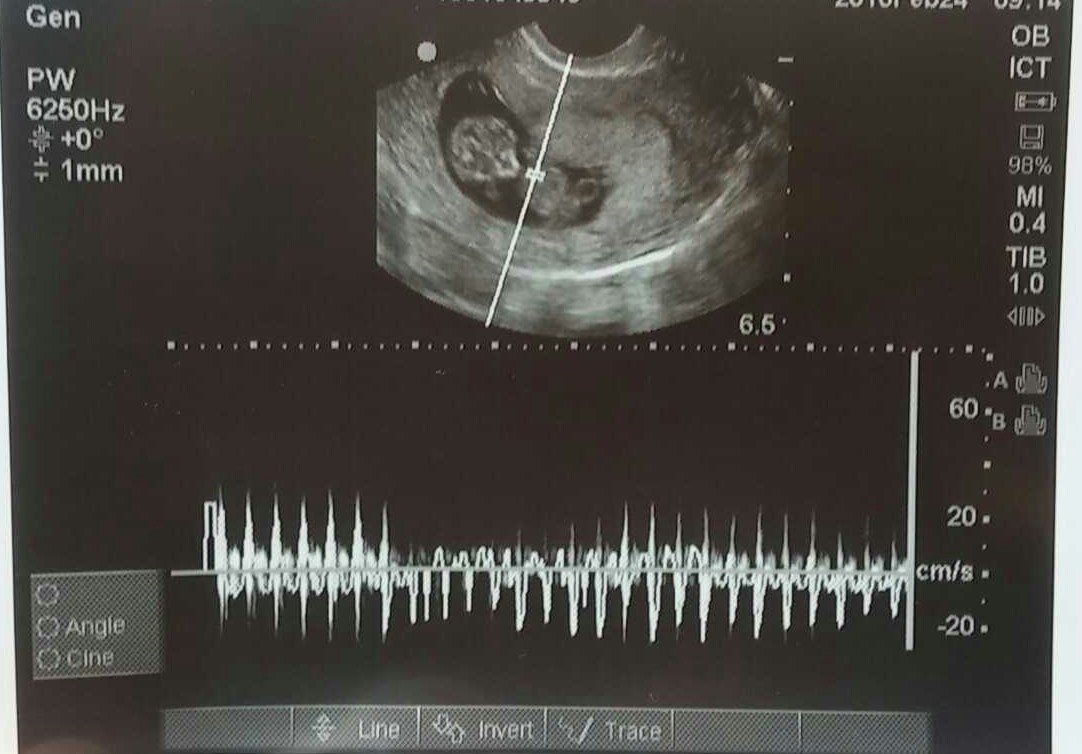

Finally! Met our rainbow baby yesterday, measuring spot on at 10w+1 and heartbeat at about 150/min. LO had the sweetest hiccups that we could see on the u/s, I'm in love!